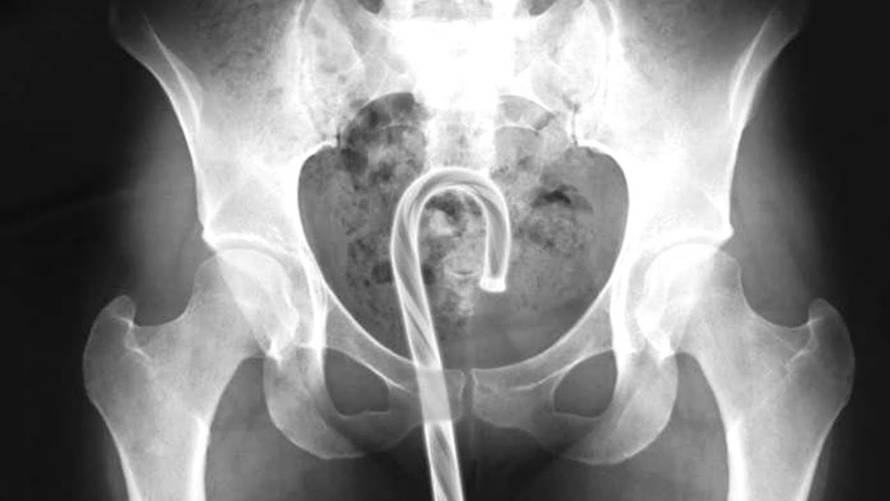

Boce i vibratori više se i ne čine toliko bizarnima jer rendgenske snimke prikazivale su i ključeve, oružje, dječje igračke, žarulje, bilijarske kugle te mobitele